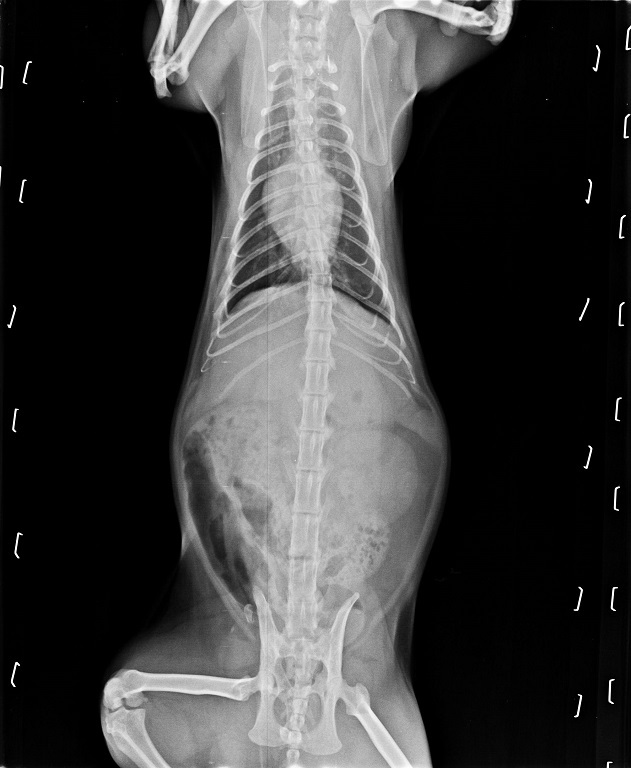

抱抱剛住院時肝指數高達840為嚴重肝炎,

不停的嚴重嘔吐拉水痢,

檢驗之後也發現腸胃道裡有大量黴菌滋生,

每天需要服用的藥物非常多,

肝藥、止吐止瀉、抗黴菌藥、抗生素和類固醇等等....

且抱抱的眼睛也因病毒感染的關係產生病變,

需要持續點抗生素眼藥水和抗病毒眼藥水。

抱抱驗肝指數有比之前剛出院時下降許多,

抱抱血檢中肝指數已下降很多,

醫生說打皮下點滴可減量成兩天打一次125ml即可,

並且口服藥物也可減量一些,

眼睛的情況也好轉許多,

抗病毒眼藥水可不用繼續點。